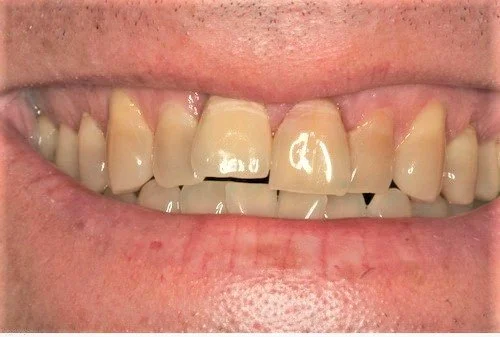

A healthy 40 year old gentleman presented with tooth 21 which was unrestorable due to gross internal resorbtion. He is a non- smoker with excellent oral hygiene.

Tooth 21 was removed and due to excellent primary stability being achievable, with good interproximal bone height (Tarnow 1998) a Replace Select implant was placed immediately, with 40+ Ncm of torque being achieved. This allowed for placement of an immediate provisional restoration. The patient’s natural crown was used along with a titanium provisional abutment to construct a pleasing provisional restoration.

The photo below shows the post operative result one hour after extraction. Note the relative continued eruption (and alveolar bone growth) of the surrounding dentition compared to implant crown 11 placed 20 years ago. This is a common problem when implants are placed in young patients in the aesthetic zone.